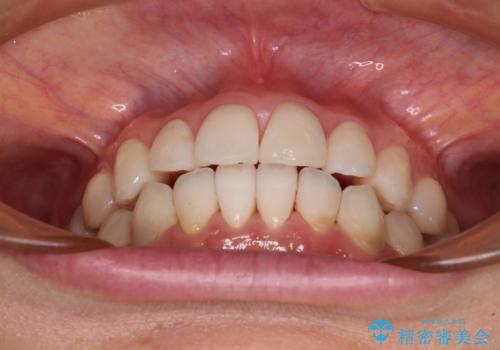

インビザライン・ライトによる矯正治療であったので、時間をかけずに治療を終えることができました。

口を開ける度に目立っていた銀歯もセラミックで自然な口元の印象となりました。